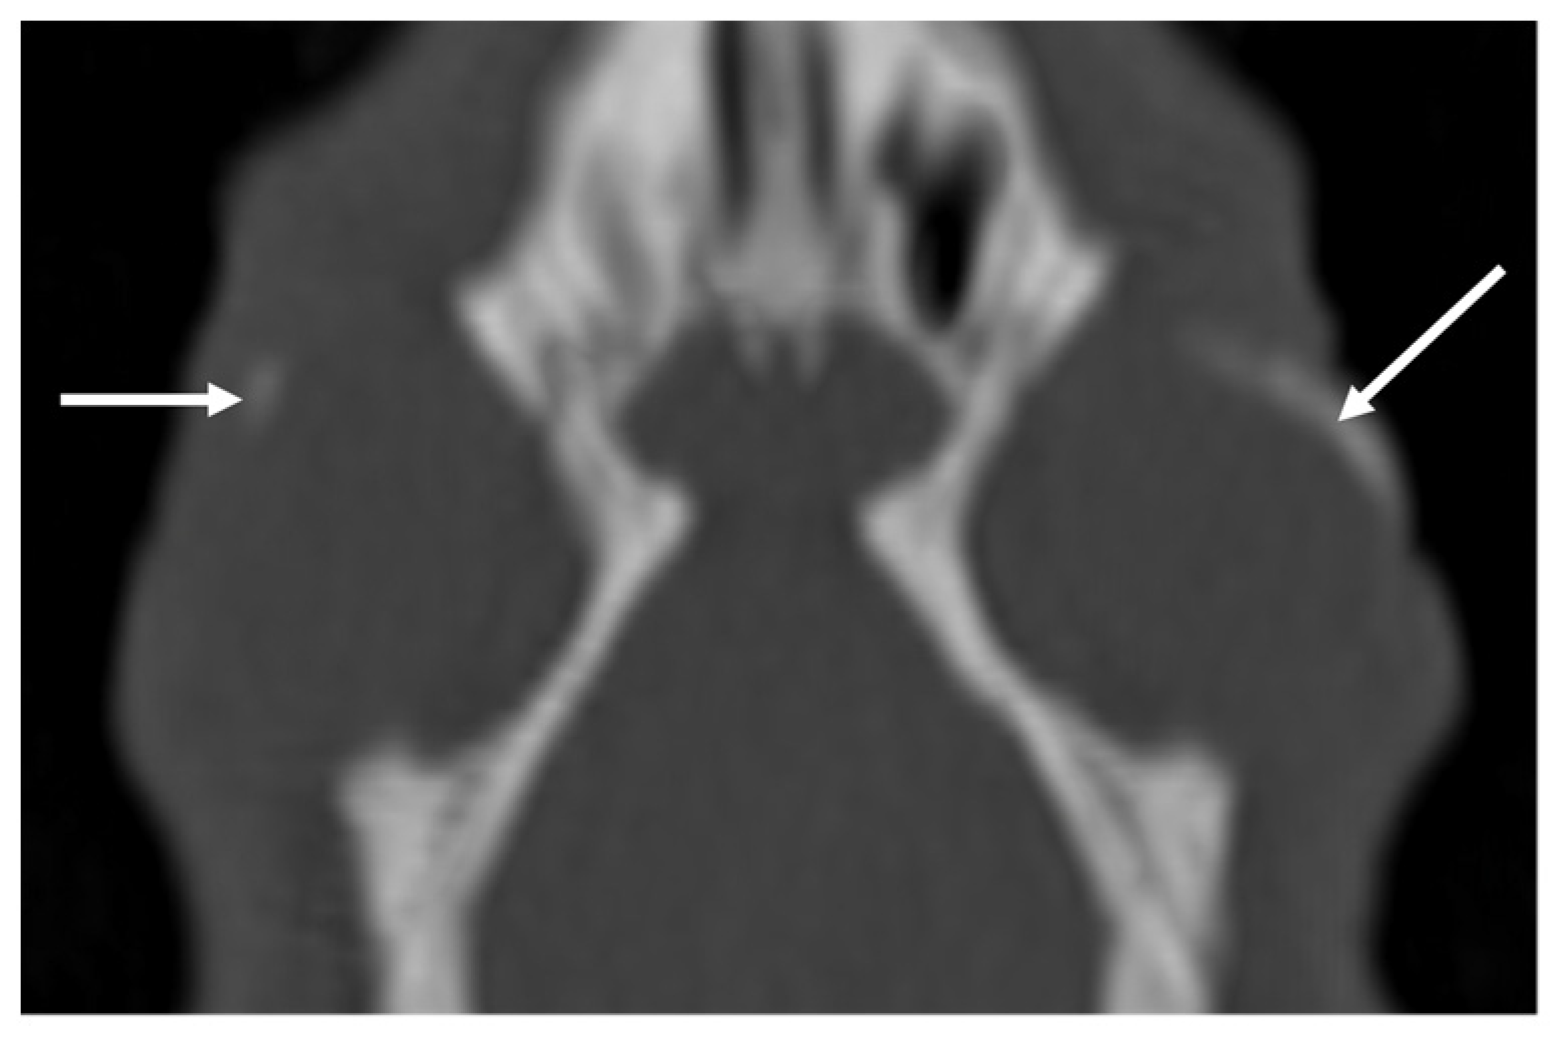

| Eye | Exophthalmos (1/0) | Deformation (0/0) | Lens luxation (0/0) | Others: mineralization (0/26) |